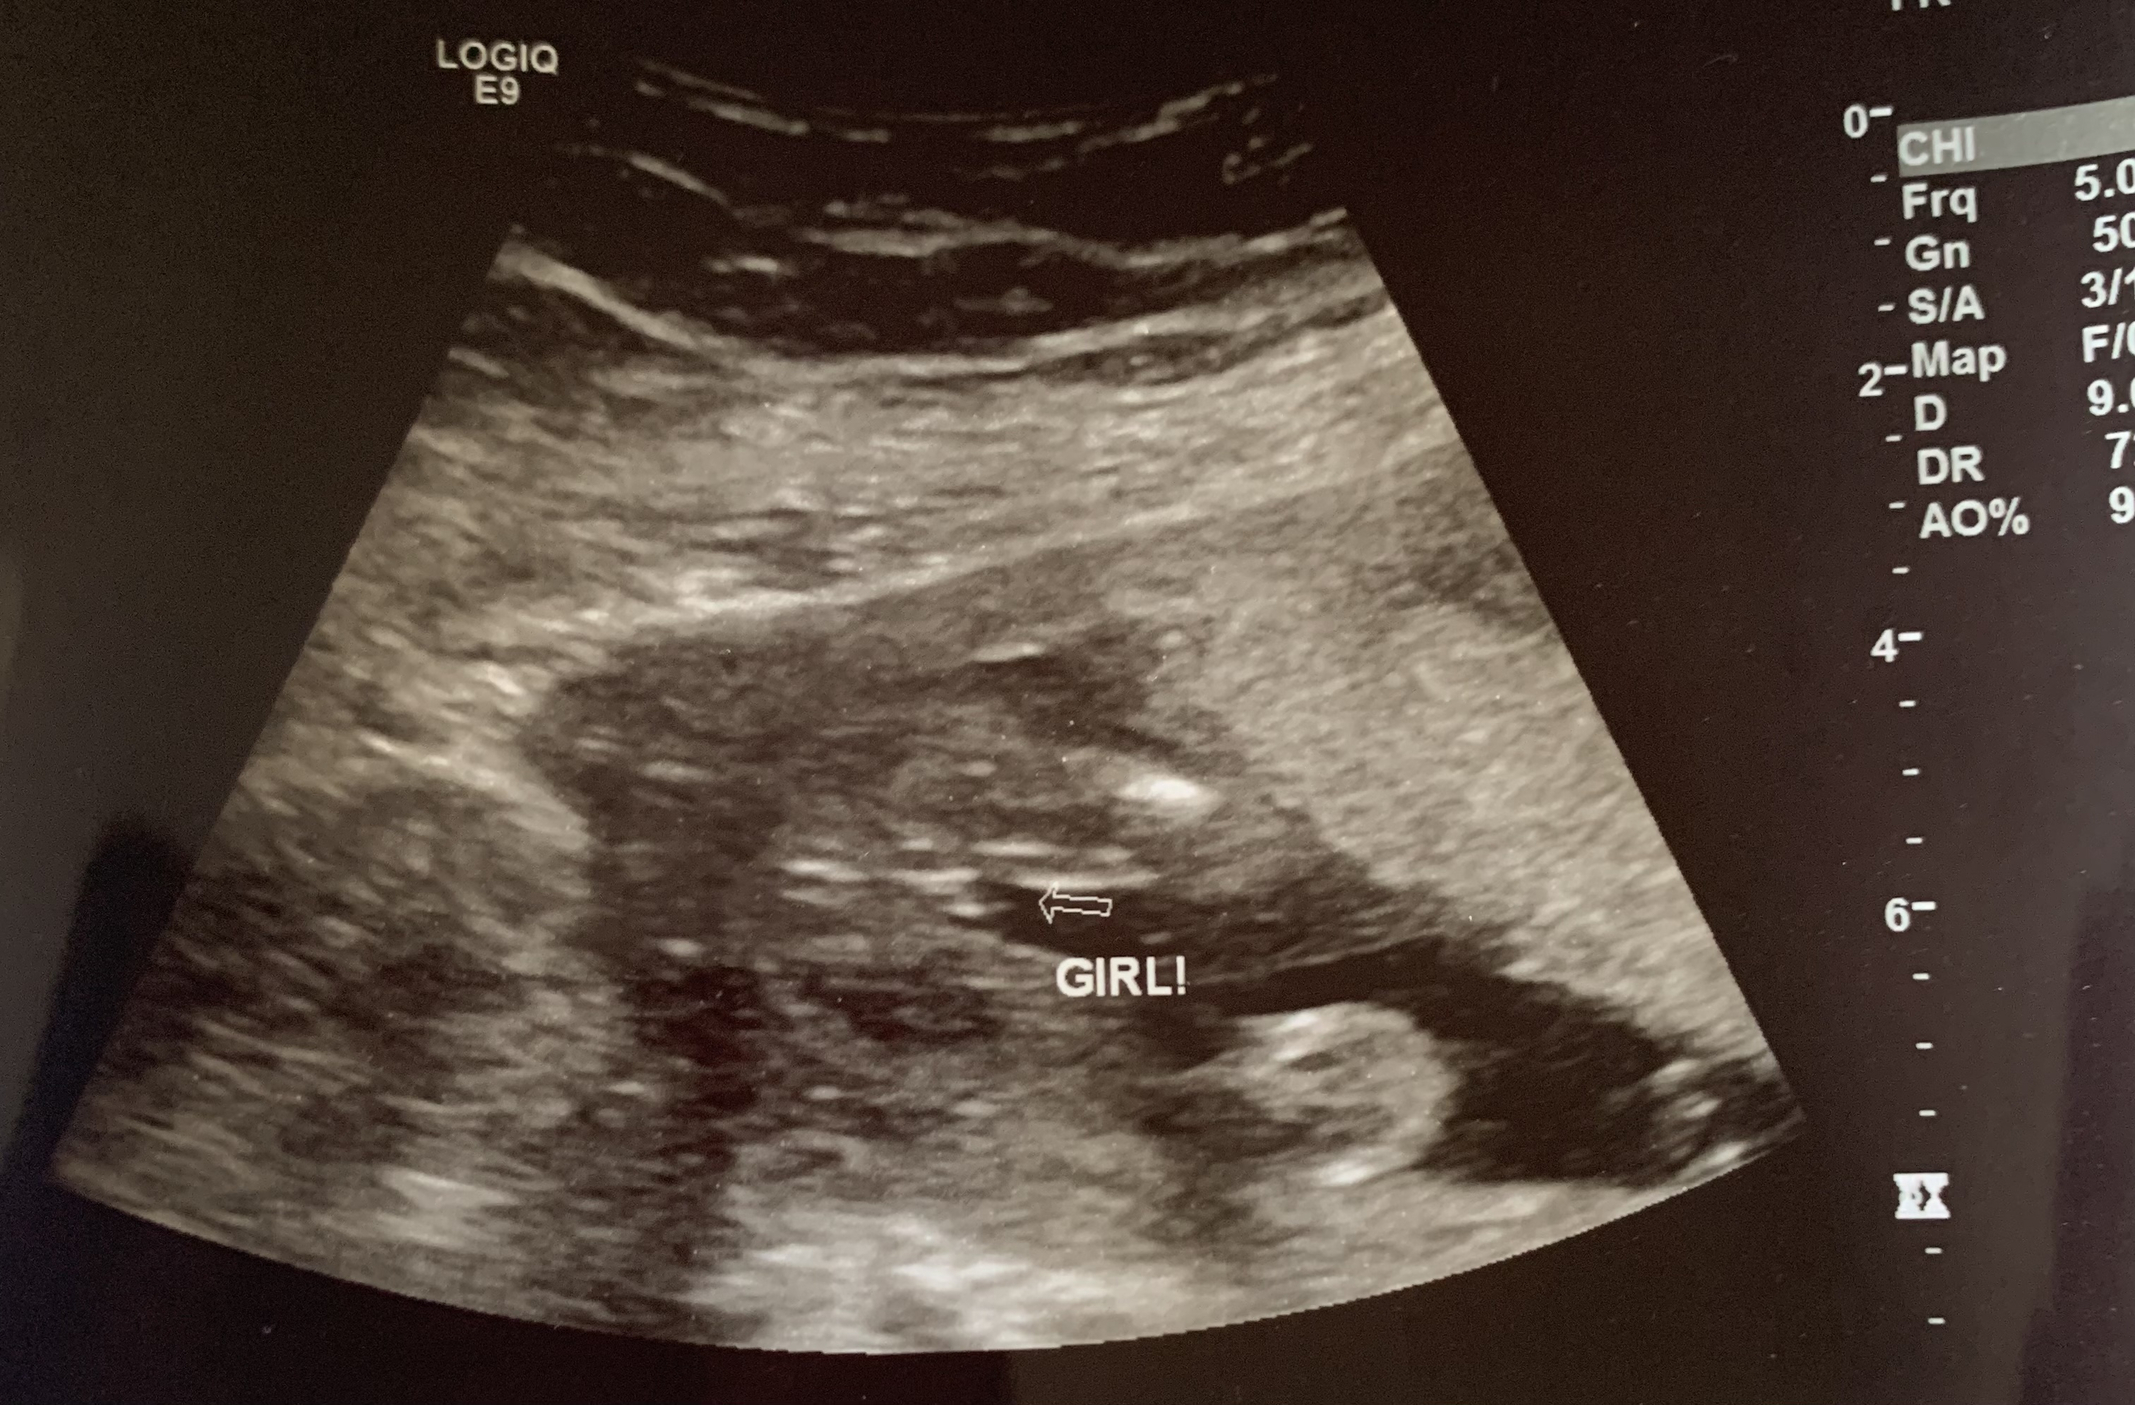

Baby GIRL (!!!!) at 19w+1d today. She was quite the little wiggler today so I need to go back on the 24th to get clearer images of the profile and placenta. I had a really lovely student and their supervisor so I got to hear about everything we were looking at the whole way through. Didn't seem to be any red flags!

Here's her cute one